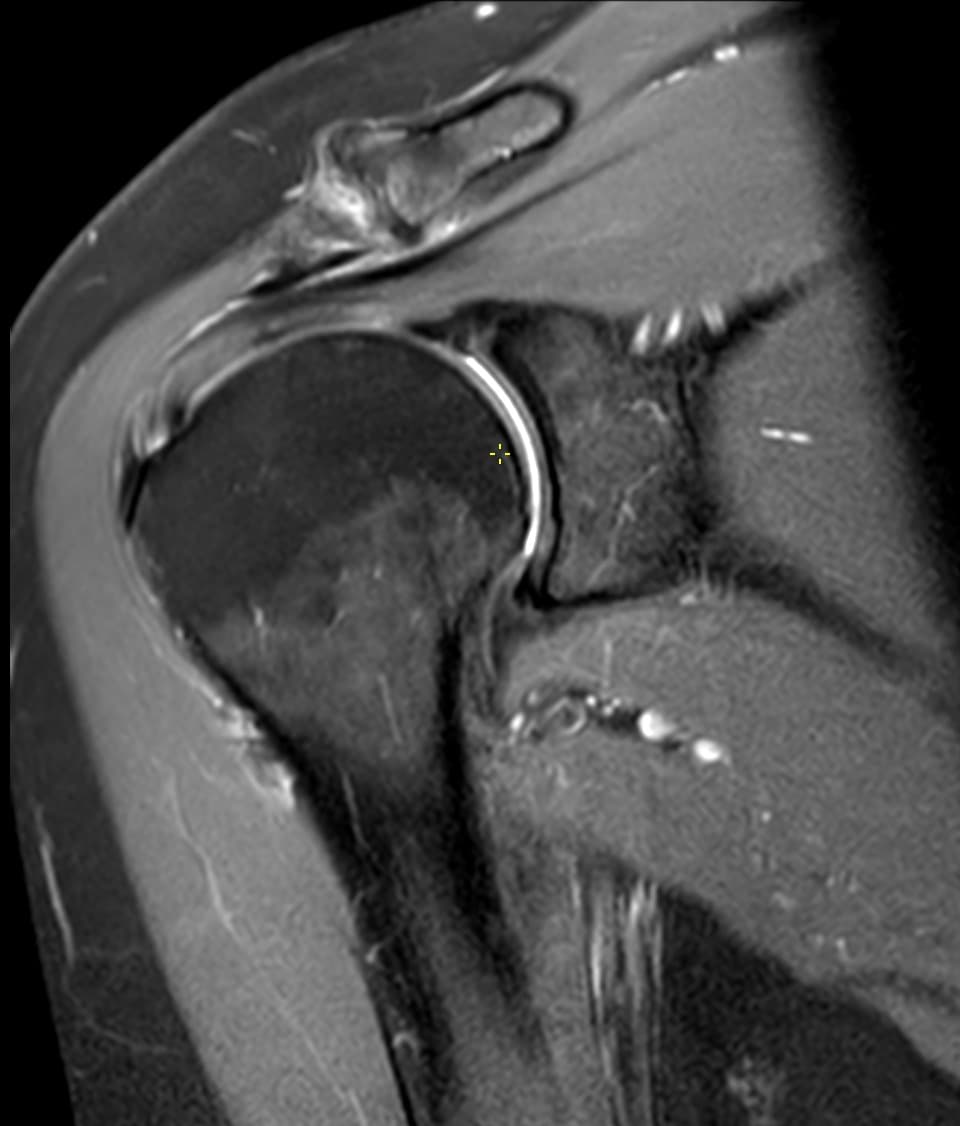

Hvornår giver en muskuloskeletal second opinion mest værdi?

Praktiske henvisningssignaler for klinikere og patienter ved uklare eller modstridende MSK-MRI rapporter.